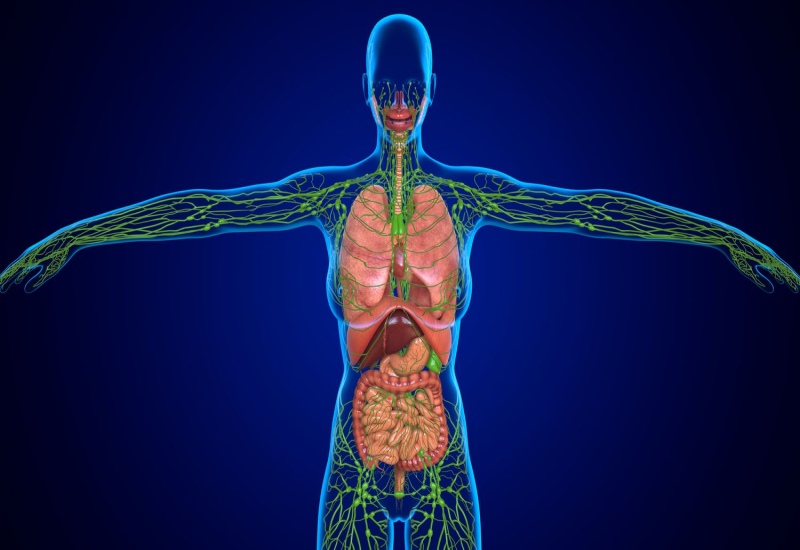

Vai trò hệ bạch huyết trong cơ chế thải độc

Hệ bạch huyết đóng vai trò rất quan trọng trong cơ chế thải độc và duy trì cân bằng sinh lý của cơ thể. Đây là một phần của hệ miễn dịch và hệ tuần hoàn bạch huyết, giúp vận chuyển các chất lạ, vi khuẩn, virus và các sản phẩm chuyển hóa dư thừa ra khỏi mô và máu.

Hệ bạch huyết thường bị nhầm lẫn là hệ “lọc độc máu”. Thực tế, hệ bạch huyết không làm sạch máu mà làm sạch dịch kẽ quanh tế bào với chức năng chính là:

- Thu nhận chất thải từ mô: Hệ bạch huyết giúp thu gom dịch dư thừa và chất độc trong mô, góp phần cân bằng áp lực và giảm phù nề.

- Lọc và tiêu diệt tác nhân gây hại tại hạch bạch huyết: Hạch bạch huyết là nơi tập trung các lympho bào T và B và đại thực bào, giúp nhận diện và phá hủy vi sinh vật hoặc tế bào bất thường.

- Vận chuyển các sản phẩm thải ra khỏi cơ thể: Các chất thải hòa tan trong bạch huyết cuối cùng được đưa tới gan, thận để chuyển hóa hoặc bài tiết ra ngoài cơ thể.

- Hỗ trợ hệ miễn dịch và chống viêm: Hệ bạch huyết giúp cơ thể nhận biết sớm các mầm bệnh, kích thích phản ứng miễn dịch giúp giảm gánh nặng cho gan và thận.